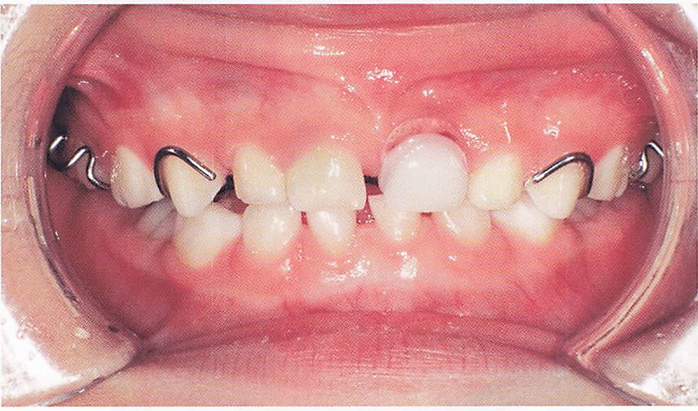

矯正歯科診断用の資料の写真を別に示す。 この資料で分析できるのはどれか。2つ選べ。

a.オーバーバイト

b.咬合平面の傾斜度

c.上下顎骨の前後的位置関係

d.アーチレングスディスクレパンシー

解答を見る

a.d